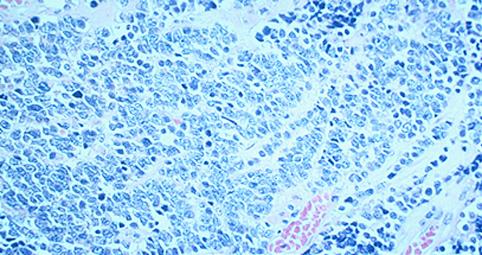

질환(병리주체)의 분류 악성 상피성종양/기타

부위(장기별) 대장/S상

검사방법 마이크로

종양의 육안분류 0형(표재형)/IIa형(IIa+IIc)

종양의 최대경(밀리미터) 15~19

종양의 심달도 sm